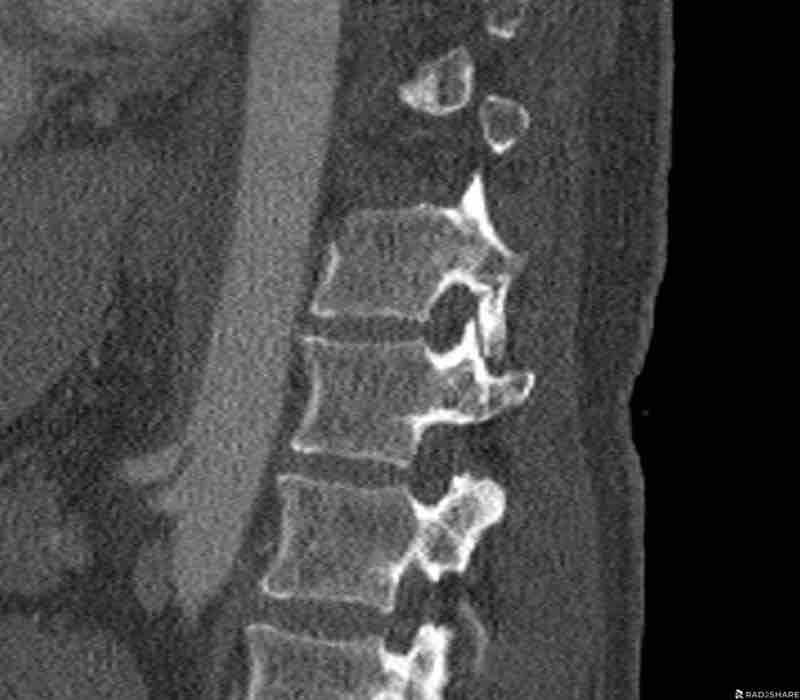

What is the AO-type of the vertebral body fracture based on only these two inages?

Findings:

- Fractures of the vertebral body with involvement of upper endplates (1 points) and posterior wall (2 points)

- Bulging of the posterior wall without any other signs of dislocation is the result of the burst fracture.

Therefore no C injury.

Conclusion

Injury type A3